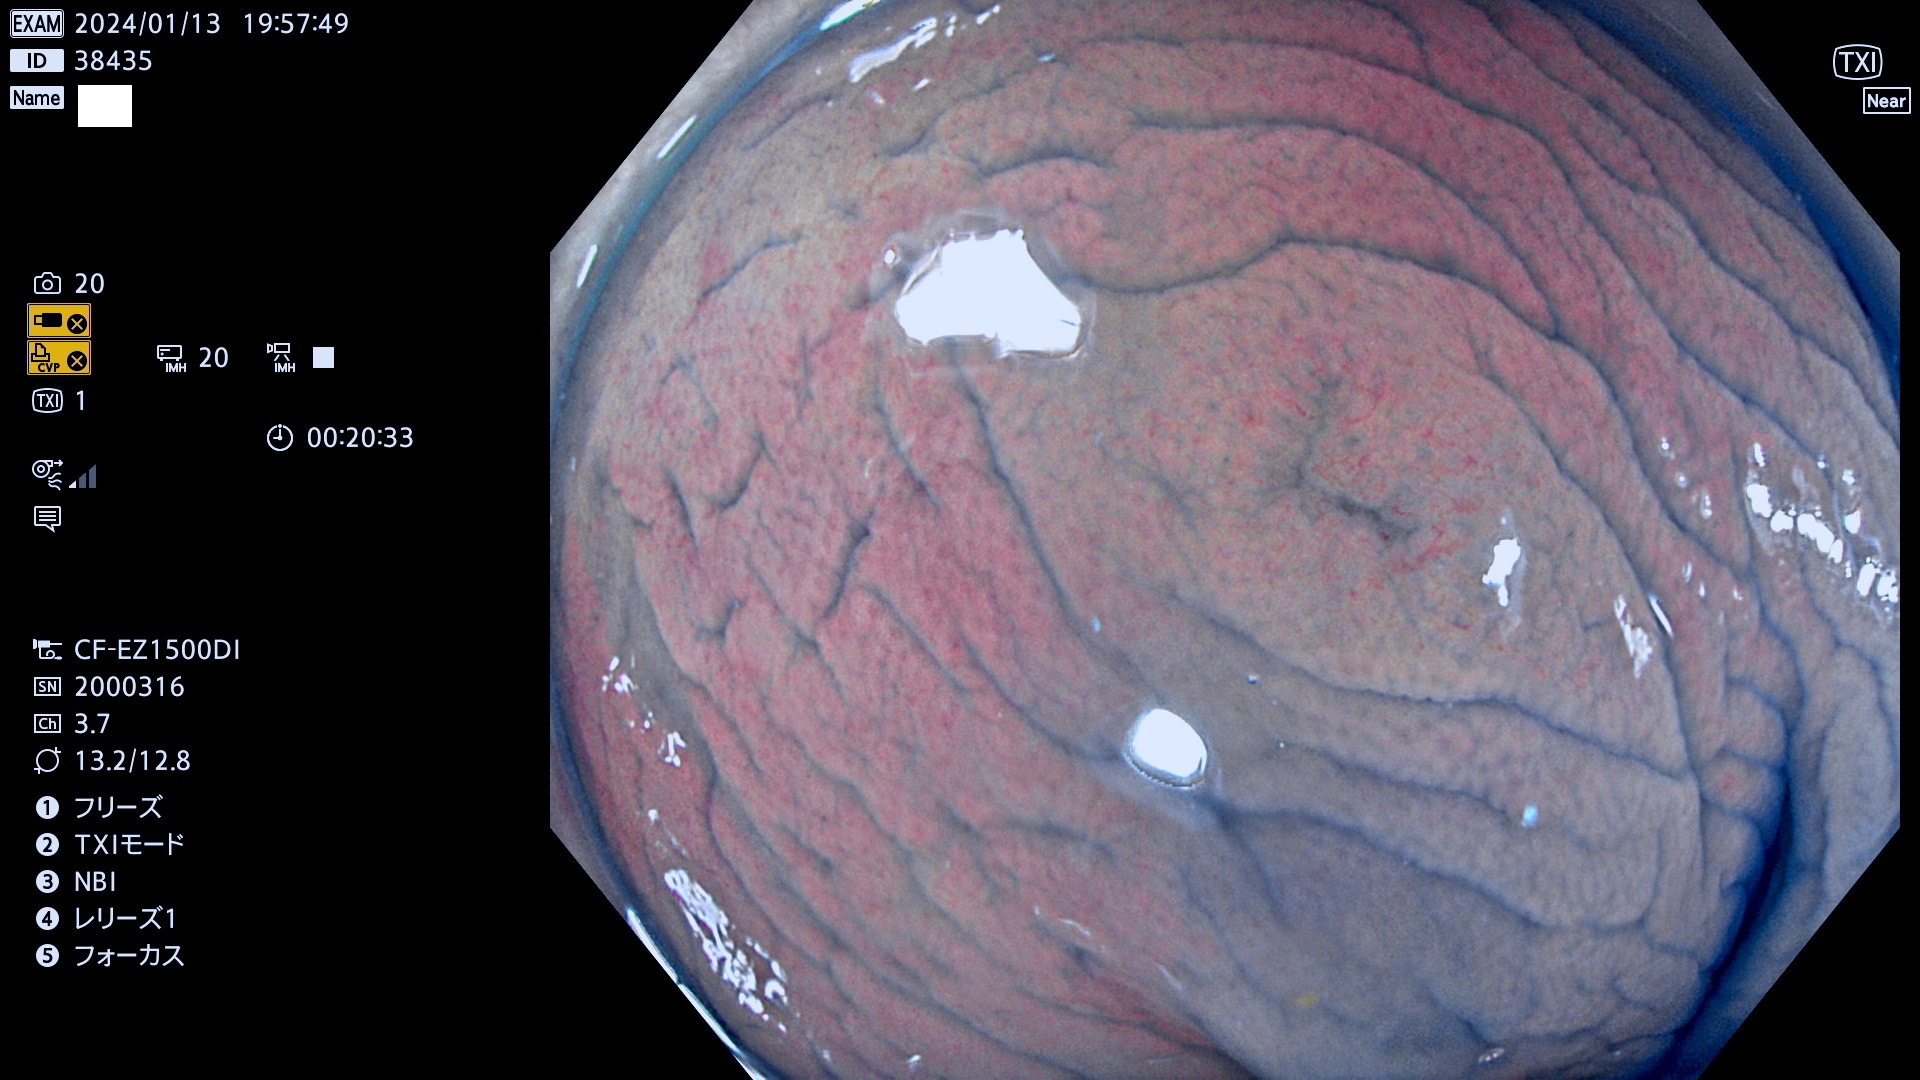

表面型腺腫(Flat Adenoma)の中で、完全に平坦な物をUb、陥凹している物をUcと呼びます。平坦隆起型(Ua)よりも、発見が難しく危険な病変です。

毎週の検査(木・金・土・日)に発見されたUb、Uc型・腺腫を、その週の日曜の夜にUPし1週間、提示します。

抽出の対象期間 2024年1月11日(木))〜1月14(日)の4日間(40件の検査)9件